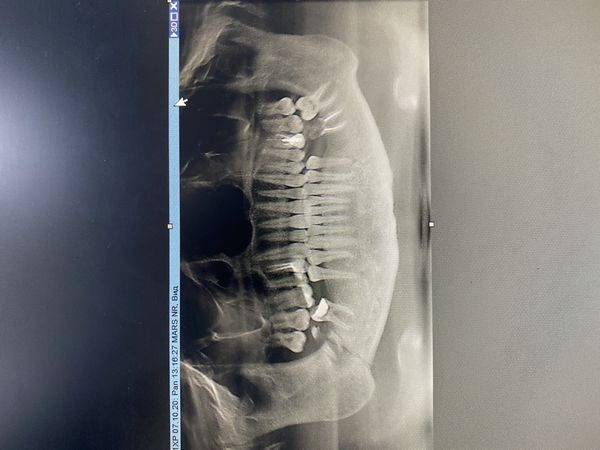

На ортопантомограмме было видно линию перелома, которая проходила через корни 48-го зуба и всё тело нижней челюсти. Существенного смещения не было.

Односторонний перелом нижней челюсти справа в области 48-го зуба.